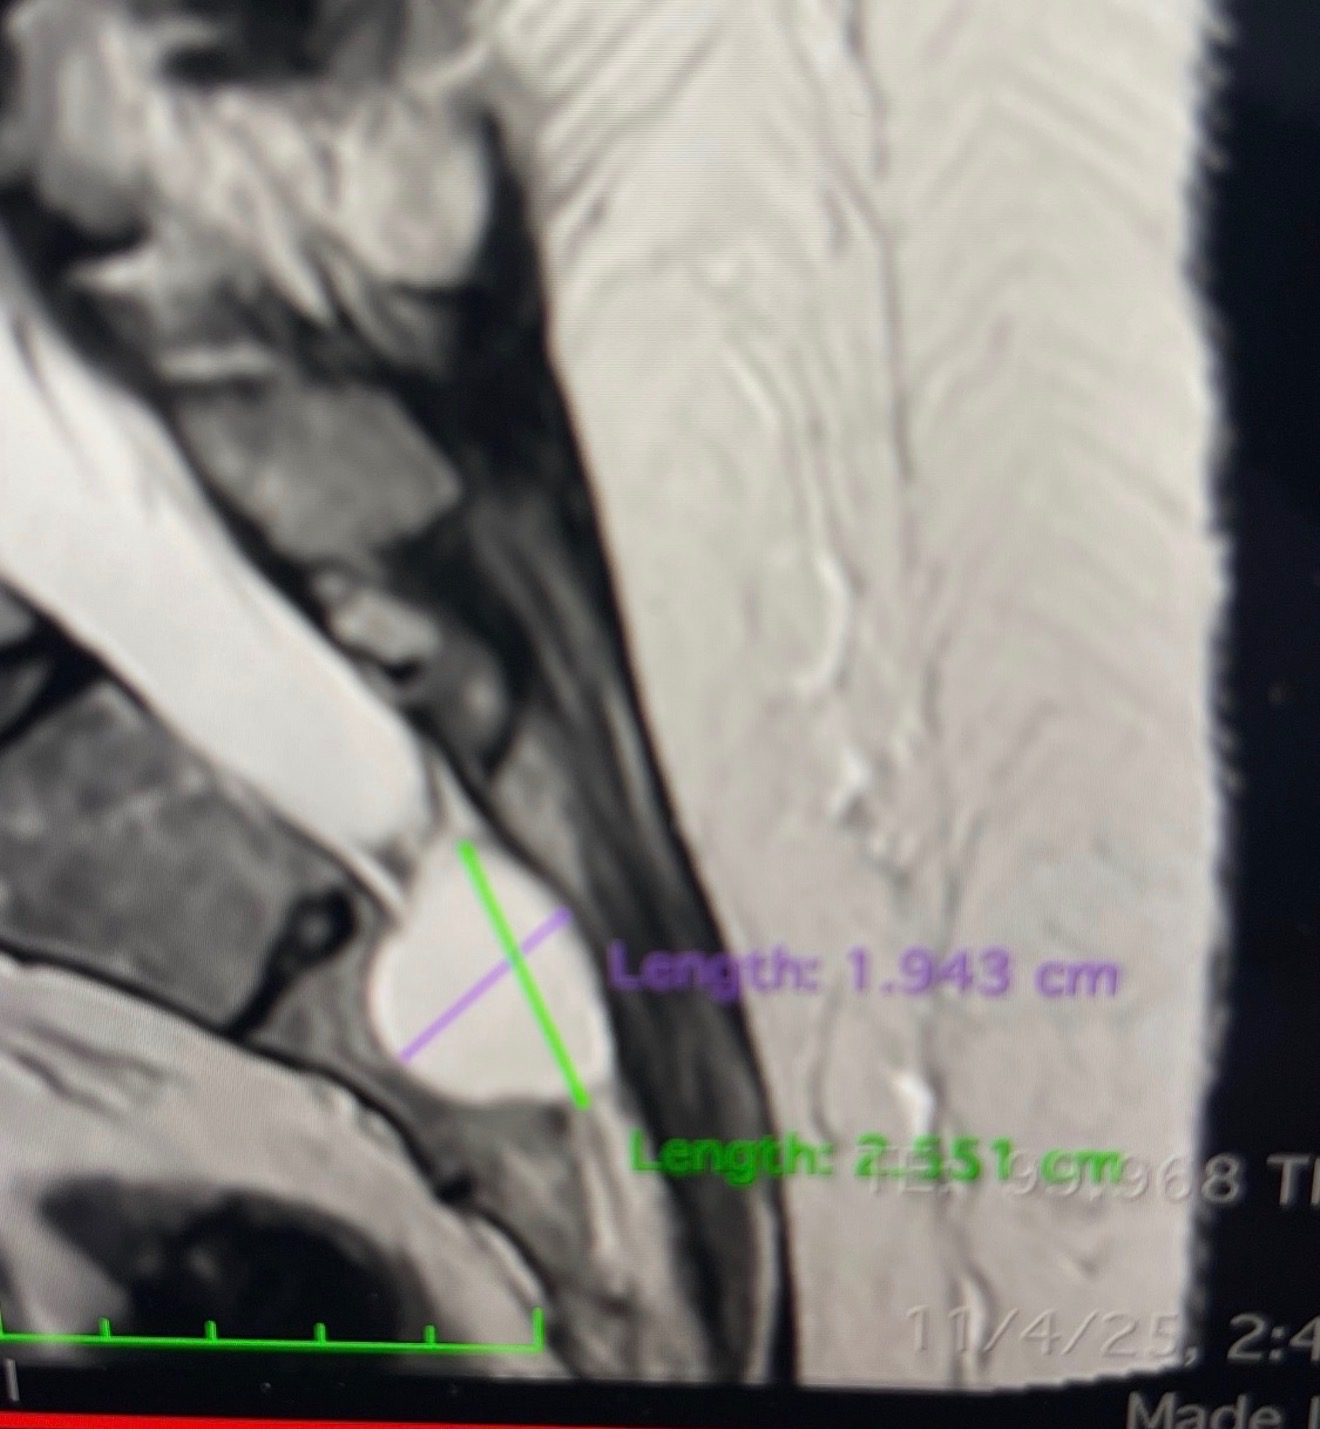

Over the past year, Karen has been living with severe, crippling pain caused by a tarlov cyst on her spinal cord, along with advanced lumbar degenerative disc disease, severe facet osteo arthritis in the lumbar spine and neuro stenosis on her L3, L4 and L5 joints. She has seen multiple doctors and specialists and has undergone X-rays, MRIs, and several CT scans. In an effort to manage the pain, she has undergone multiple cortisone injections— none of which have brought lasting relief. After multiple consultations she was also not a candidate for nerve ablations.

Recently, doctors discovered that the cyst on her spine is progressing and is now dangerously close to leaving her wheelchair-bound. She is unable to stand for more than 10 minutes at a time and lives in constant pain, day and night. She cannot lie flat, struggles to sleep, and her quality of life has been deeply affected.